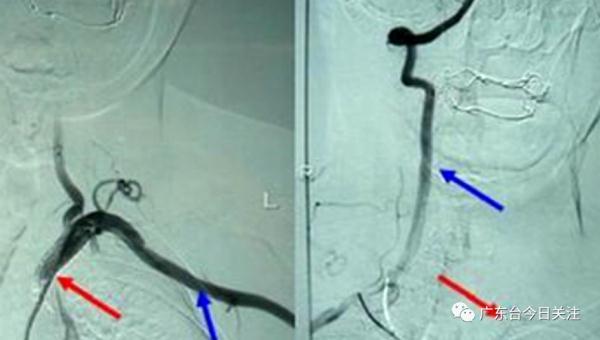

经医院初步评估,小美的症状符合脑卒中,进一步完善头颈CTA检查,发现小美得了一种名叫“东方美女病”,学名称为“大动脉炎”的疾病,这种疾病跟饮食,有密不可分的关系。

“‘东方美女病’好发于东亚女性,一般是30岁以下,目前病因不详,一般认为考虑跟感染后诱发免疫调节,免疫应答异常,累积到大动脉血管炎造成的。”